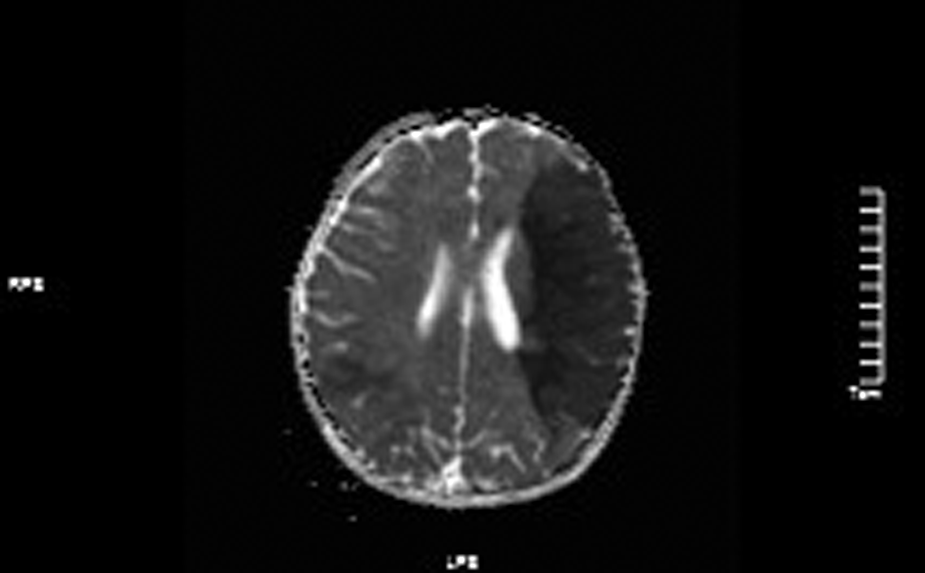

Figure 4

ADC values decreased in the left frontotemporal lobe and the right temporo-occipital lobe.